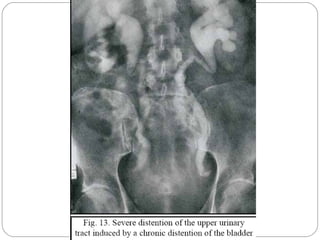

The postvoid image may also be helpful in evaluating

patients with upper urinary tract dilatation.

Persistence of the dilatation on the postvoid image

suggests fixed obstruction,

The postvoid image is most helpful in assessing

residual volume.

Grading of hydronephrosis

 Gr 1-dilatation of renal pelvis without dilatation of calices, prominent

reflex of renal sinus without signs of parenchymal atrophy.

 Gr2-dilatation of renal pelvis and calices ,pelvicalyceal pattern is

maintained, no signs of parenchymal atrophy

 Gr3-moderate dilatation of renal pelvis and calyces ,blunting of

fornices and flattening of papillae, mild cortical thinning may be seen

 Gr4-gross dilatation of renal pelvis and calyces which appear ballooned

,loss of borders between renal pelvis and calyces,renal atrophy seen as

cortical thinning.